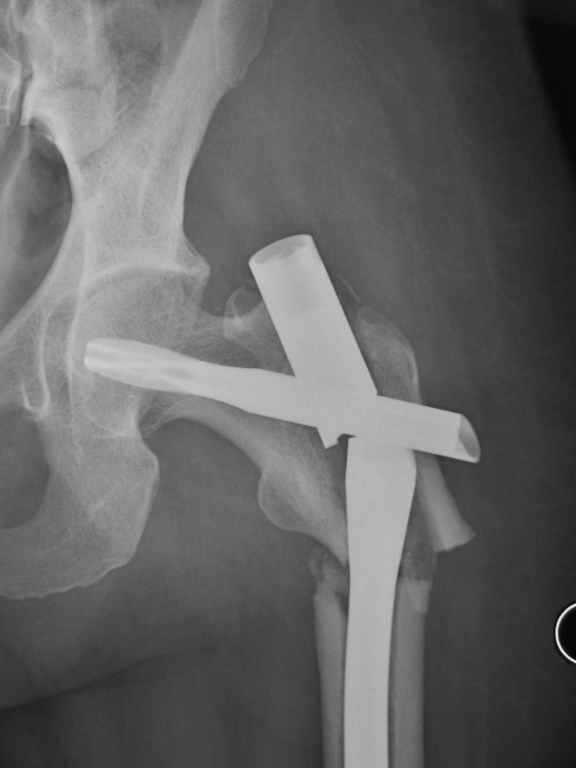

I was wondering if you could give me your thoughts on a case. 50 yo female with breast cancer who had pathologic fracture of proximal femur. Originally fixed with PFN which has broken.

Tough case. It should have healed, I think it was the right implant.

Was it in varus to start? Too much stripping w/ the reduction?; or poor protoplasm and cancer. On the lateral it looks like the piriformis starting point was reamed w/ starting point too posterior and aiming too ant. and med. This is a common problem w/ this fx and the proximal piece ends up

flexed, ER and in varus. This may have contributed to failure, but this deformity will be the same challenge on the revision. Do you have

initial post op xrays.